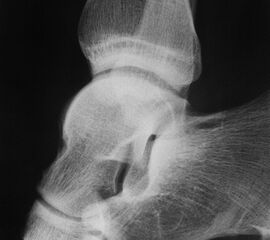

Besondere Bemerkungen zum Beispielbild:

• Patient mit anamnestisch chronischer OSG Instabilität.

• Ventral der Tibia findet sich ein abgebrochener Osteophyt.

Zur Vollansicht und zum Lesen der Bildbeschreibung bitte die Bilder anklicken.